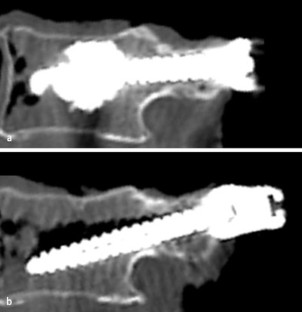

Abb. 1

Abb. 2

Abb. 3

Abb. 4